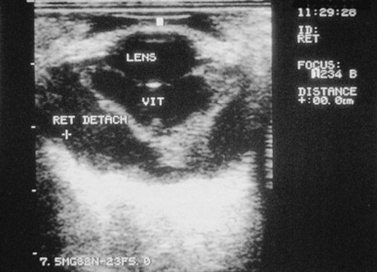

TRAUMA TO THE RETINA

Retinal tears, hemorrhage, edema, and detachment may be caused by trauma.48,49 In cases of opaque ocular media, retinal separation may be diagnosed by ocular ultrasonography (Fig. 39-9). Retinal degeneration may follow ocular trauma. Retinal hemorrhage and edema should be treated with systemic corticosteroids. With current technology, surgical repair of retinal tears, lacerations, or detachments in food animals and horses may be feasible in selected cases.

image

Fig 39-9 Ocular ultrasound of a horse eye after blunt trauma to the globe. Note the characteristic V-shaped retinal detachment.